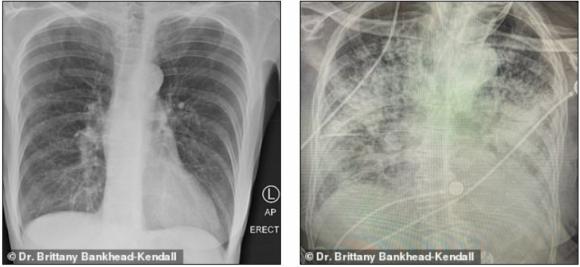

Phim của người khỏe mạnh có nhiều khoảng đen, cho thấy họ có thể hít vào đủ lượng oxy cần thiết. Phim chụp phổi người hút thuốc thì có nhiều khoảng mờ, còn của bệnh nhân Covid-19 thì gần như trắng xóa.

Phổi người hút thuốc (bên trái) và phổi bệnh nhân Covid-19 (bên phải). Ảnh: Bác sĩ Kendall.

Những khoảng mờ trên phim chụp phổi thường là chỉ dấu của dịch lỏng, vi khuẩn, hoặc tổn thương và vết sẹo.

Bác sĩ Kendall đánh giá, phổi của các bệnh nhân trải qua Covid-19 tệ hại hơn bất cứ người nghiện thuốc lá nào mà bà từng biết.